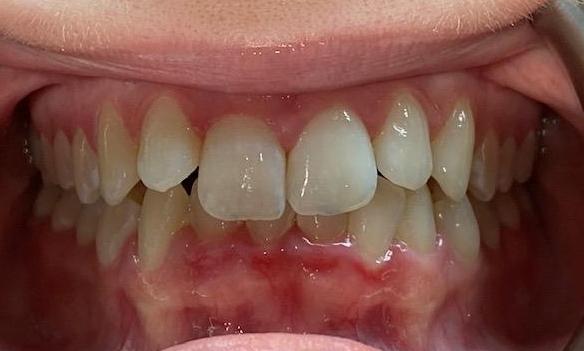

She came to us with a deep bite due to her lower front teeth sitting too high and her two front teeth pushed forward. Using Invisalign, we moved her lower front teeth down into their proper position and pulled the two front teeth back into place. She also needed a deep cleaning to removed deep buildup and restore her gum health. The results are beautiful and healthy!